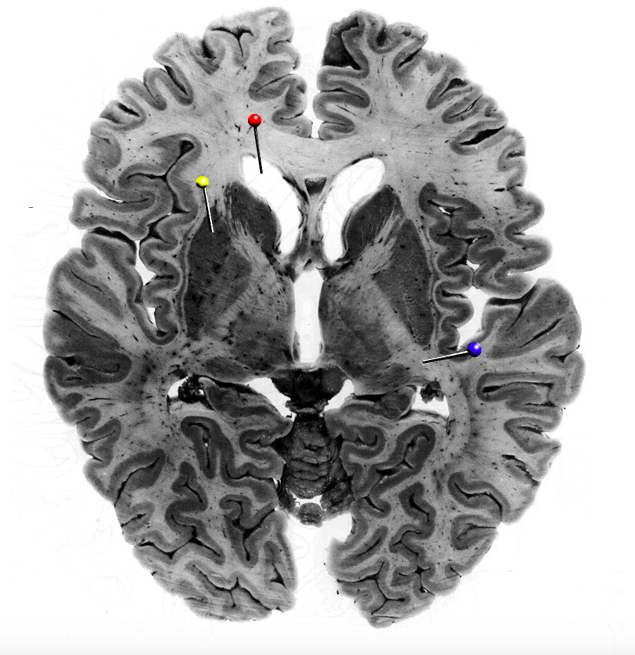

In this horizontal brain slice, the yellow pin is in

What is the structure indicated by the black pin?

?

What fibres is the structure marked by the black pin made up of?

Commisural fibres

In this horizontal brain slice, the yellow pin is in the…

putamen